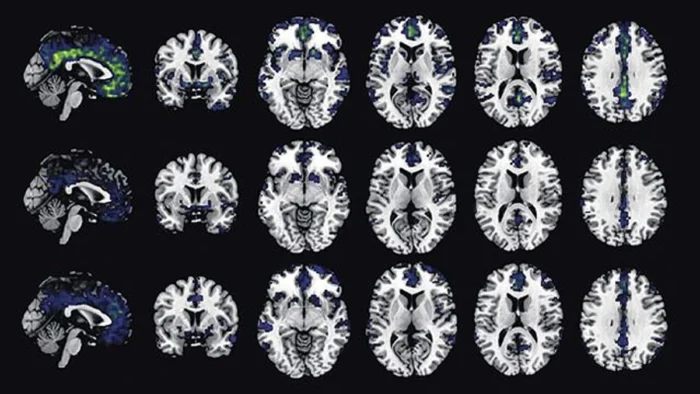

Nuevas Dudas sobre la Eficacia de Fármacos contra el Alzhéimer

Imagen de archivo: https://www.eldiario.es/ Nuevas Dudas sobre la Eficacia de Fármacos contra el Alzhéimer Foto: Archivo – Todos los derechos reservados Una reciente revisión de 17 ensayos clínicos, que involucraron a más de 20.300 pacientes, ha generado interrogantes sobre la verdadera eficacia de los medicamentos antiamiloides en el tratamiento del Alzheimer. El análisis sugiere que […]